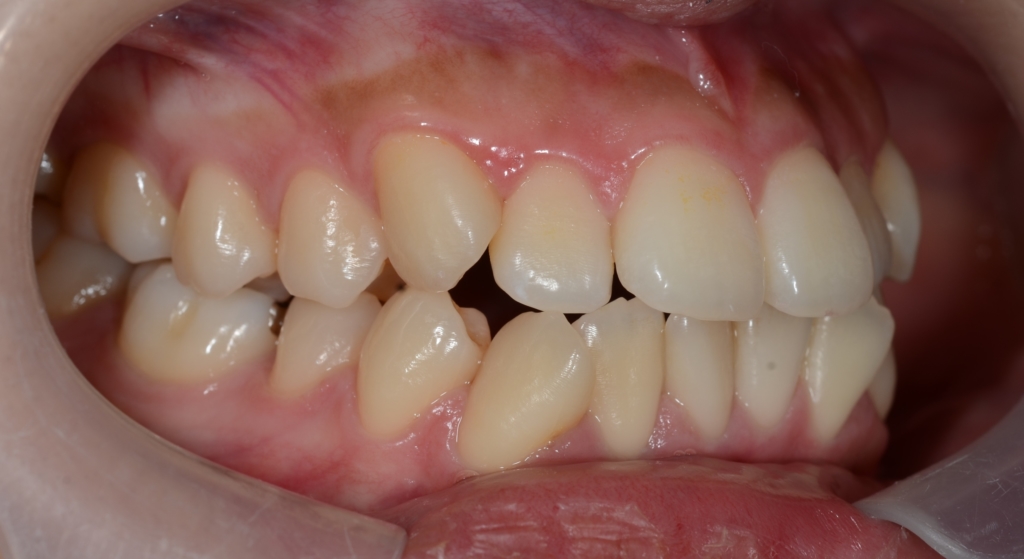

【Before】

しかし、お口を閉じていても、上の前歯がチラリと見えています

この患者さんの場合、

【診断】

#1.上下顎前突

#2.歯と顎の不調和による軽度の叢生

と診断しました。